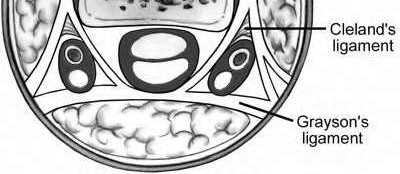

A 50-year-old woman is diagnosed with carpal tunnel syndrome. She is prescribed a cock-up wrist splint at 30 degrees of extension to wear at night. This splint has what effect on the carpal tunnel?